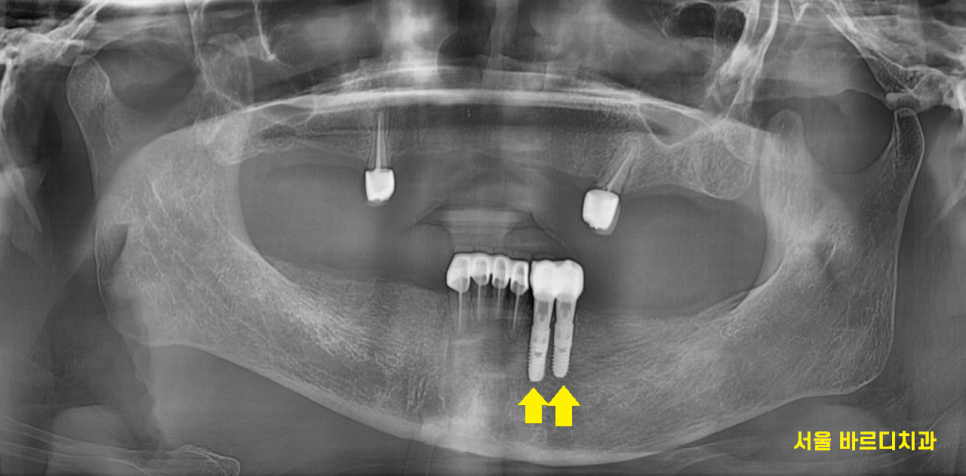

240125

틀니 사용중 치아 부러짐

문제의 치아 깨끗하게 발치한뒤

임플란트 2개를 식립해드렸습니다.